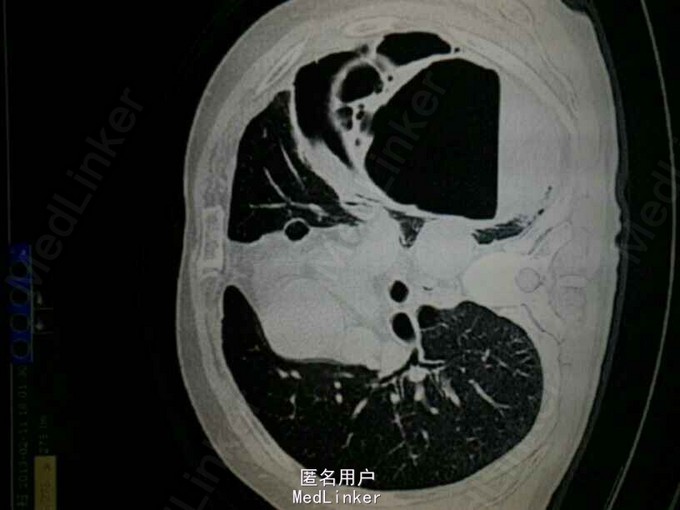

查体:左肺叩诊鼓音,左肺呼吸音低,左下肺可问及少量湿啰音。 辅助检查: CT提示:左肺多发大小不等的囊状气腔,部分病灶壁较厚,可见液平。左肺可见斑片状渗出。左侧胸腔积液。考虑左肺多发肺大泡伴感染,左侧胸腔积液。双肺气肿。

诊断: 肺大泡 肺部感染 胸腔积液 入院以后一直体温高,最高可达39.9度,予头孢呋辛及泰能抗感染治疗,体温无法好转,考虑肺大泡内部并发感染及脓液,予胸腔闭式引流,见较多积脓引出,十余天抗感染后体温白细胞逐渐改善,并行左侧剖胸粘连松解肺大泡切除